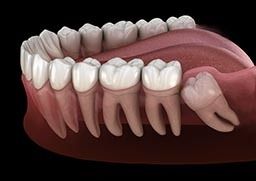

“Wisdom teeth” is the common name for the third molars. There are typically four wisdom teeth. They are the farthest back tooth on each side of the upper and lower jaws, and their location and large size make them perfect for grinding food. They are vestigial teeth from our hominid ancestors who had to grind tough, fibrous vegetables. Genetic variation in jaw and tooth size, a diet less stimulating to jaw growth and lack of tooth loss contribute to a lack of space for the wisdom teeth. In a healthy mouth with enough space, the third molars may not need removal.

The physical eruption of wisdom teeth can cause discomfort. Erupted third molars are often malformed and can be associated with weakened soft tissue. They are difficult to clean, which also makes them susceptible to decay and soft tissue infections.

Approximately one-third of all wisdom teeth do not fully erupt into position. This lack of eruption is called impaction. Some third molars remain deep within the jaw; others are only slightly malpositioned or have a small flap of soft tissue overlying part of the tooth. Impaction impedes proper cleaning, which can lead to a buildup of bacteria that may cause an infection. This infection, called pericoronitis, typically involves the soft tissue around the crown of a partially erupted third molar. Treatment of pericoronitis consists of oral antibiotics, chlorhexidine rinses and warm saline rinses. Problems with a wisdom tooth can lead to decay and infection in the adjacent second molar.